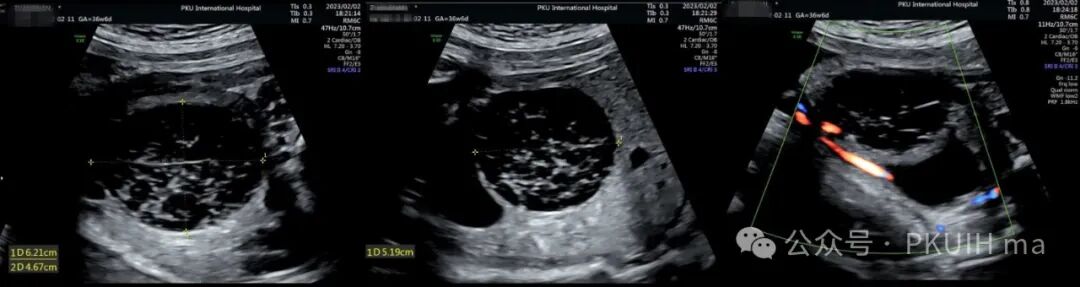

上图是一例孕36周+突然发现胎儿右下腹膀胱后方见一复杂囊性肿物,大小约6.3x5.0x5.1cm,边界清,形态规则,内回声不均匀,似囊实性改变。(该胎儿为女性胎儿)

在随后的随访观察中(如下图)发现囊肿大小和内部回声有变化。最终考虑是卵巢出血性囊肿(卵巢扭转待除外)